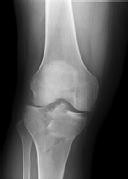

**CLINICAL SITUATION**

Figures 1 and 2 are the radiographs of a 35-year-old man who is brought into the emergency department after a motor vehicle collision. He is complaining of isolated knee pain. Examination reveals swelling, blood filled blisters, popliteal ecchymosis, joint line pain, and limited knee joint motion. His pulses and sensation are normal.

This knee injury is best described as a